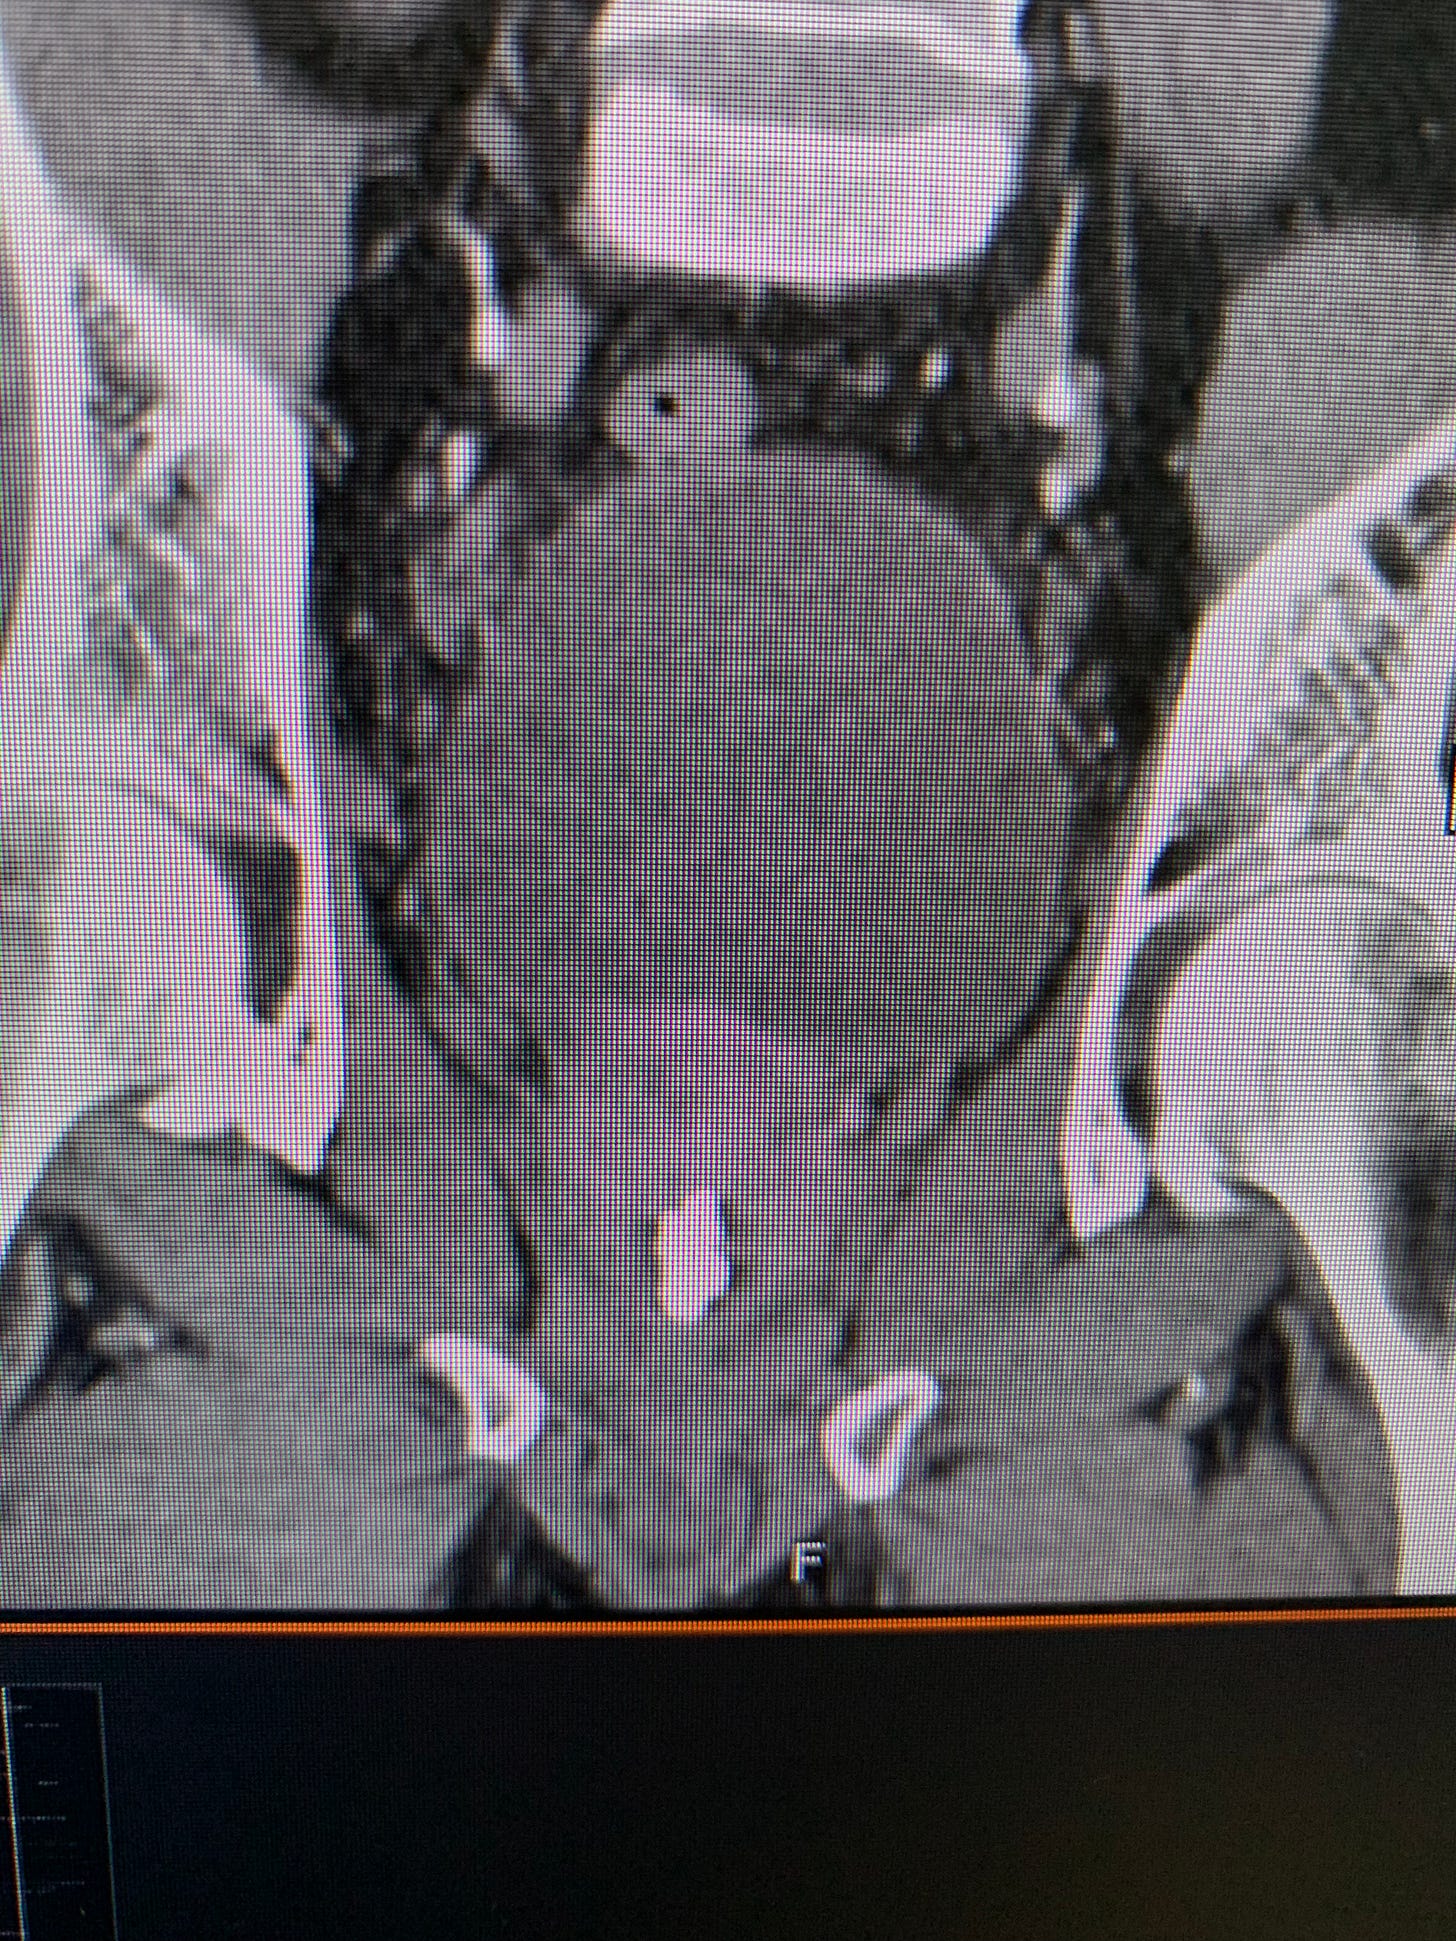

They did the scan: a monster over 10mm, bright white on the imaging, sitting in my bladder and prostate area like it had rented the place. The ER team confirmed what I already suspected—it wasn’t passing on its own.